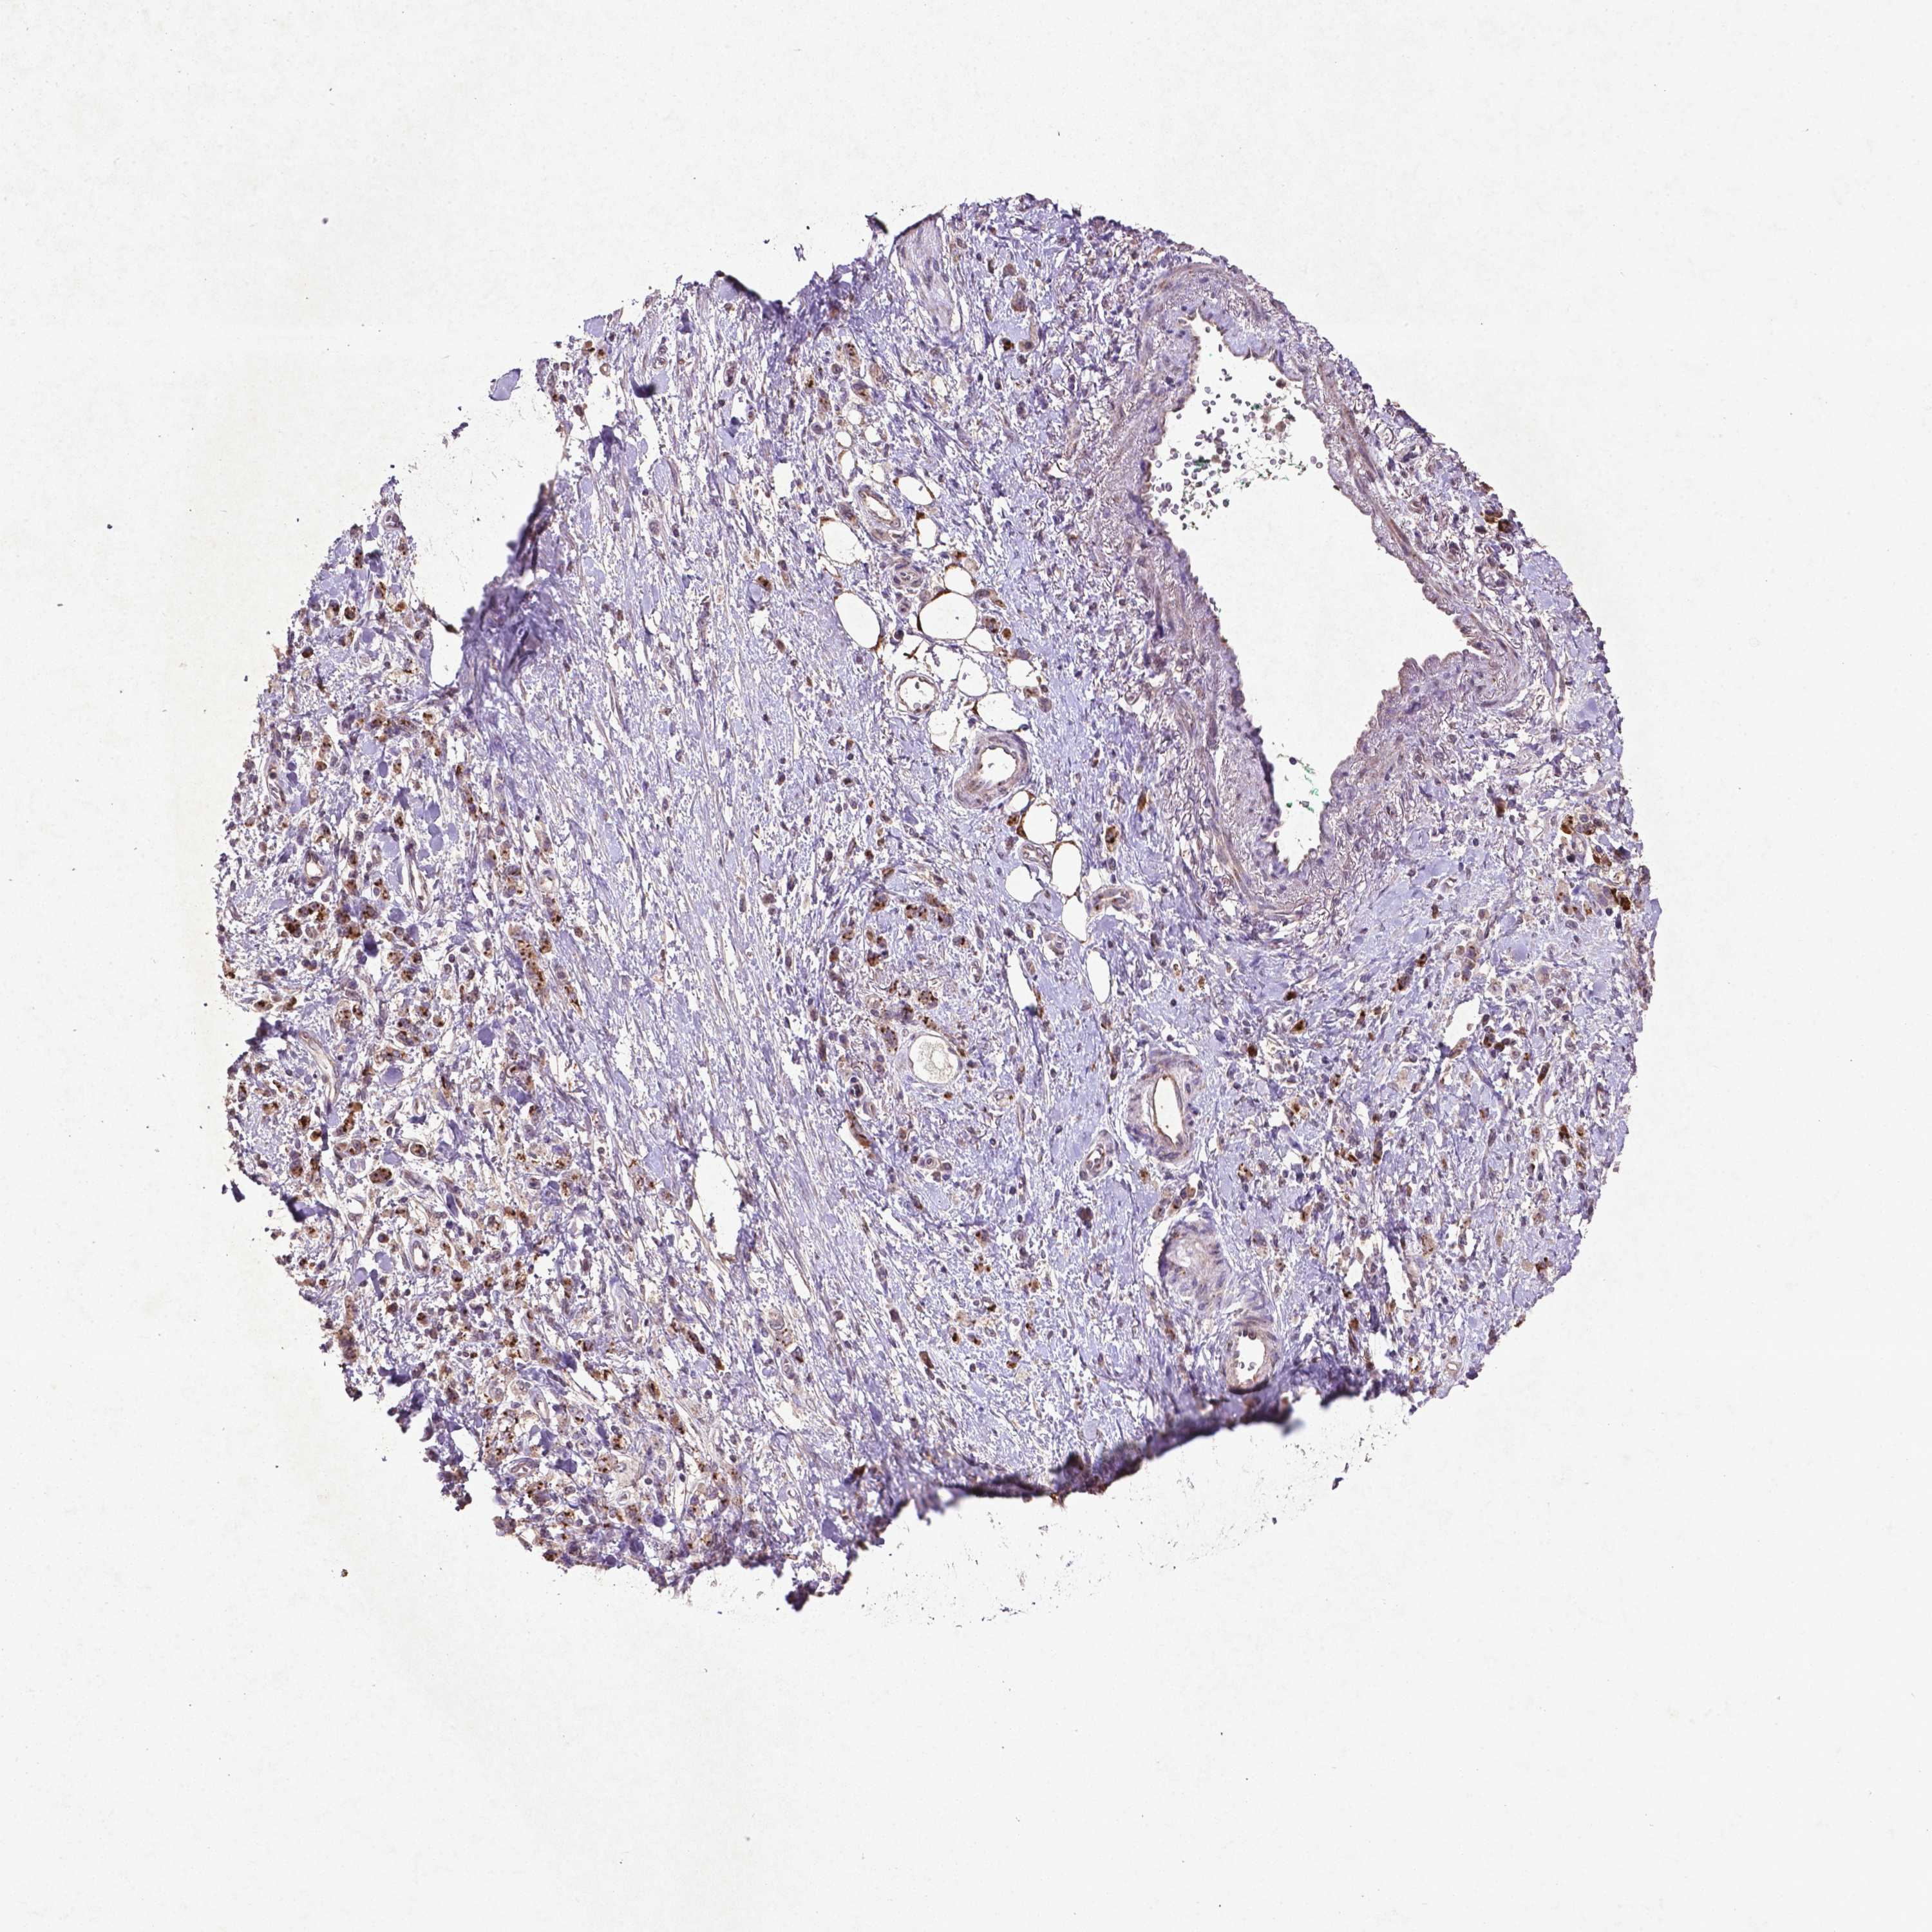

STOMACH CANCER - Protein expressioni

A mouse-over function shows sample information and annotation data. Click on an image to view it in a full screen mode. Samples can be filtered based on level of antibody staining by selecting one or several of the following categories: high, medium, low and not detected. The assay and annotation is described here.

Note that samples used for immunohistochemistry by the Human Protein Atlas do not correspond to samples in the TCGA dataset.

Antibody stainingi

Antibody staining in the annotated cell types in the current human tissue is reported as not detected, low, medium, or high, based on conventional immunohistochemistry profiling in selected tissues. This score is based on the combination of the staining intensity and fraction of stained cells.

Each image is clickable and will lead to virtual microscopy that enables deeper exploration of all samples and also displays staining intensity scores, fraction scores and subcellular localization as well as patient and tissue information for each sample.

CAB069425

CAB080053

CAB080065

CAB080070

CAB080081

CAB080095

CAB080097

Staining

High

Medium

Low

Not detected

Intensity

Strong

Moderate

Weak

Negative

Quantity

>75%

75%-25%

<25%

None

Location

Nuclear

Cytoplasmic/membranous

Cytoplasmic/membranous,nuclear

Adenocarcinoma, NOS

Adenocarcinoma, High grade